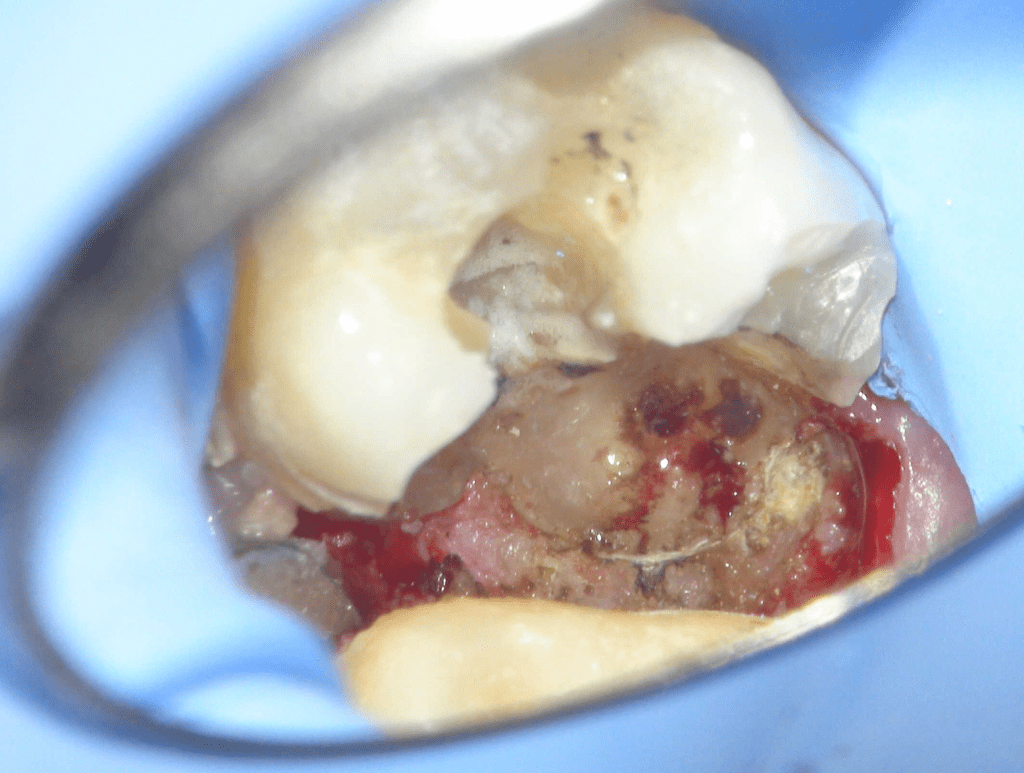

Reconstrucción preendodóntica

Reco pared vesticular